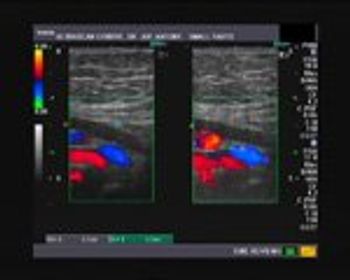

These are ultrasound images of an early pregnancy.